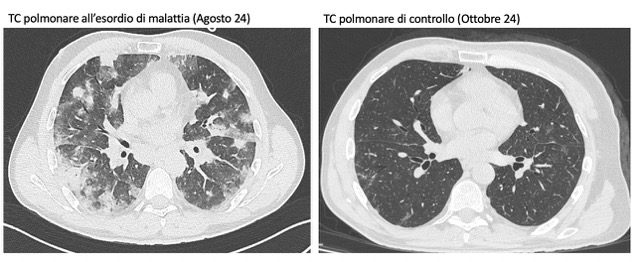

PO:22:039 | A rare form of interstitial lung disease: granulomatous and lymphocytic interstitial lung disease